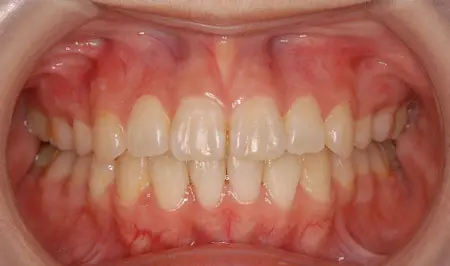

2024.08.1720代女性「出っ歯と歯のガタガタが気になる」叢生を伴う上顎前突症をワイヤー矯正で治療した症例